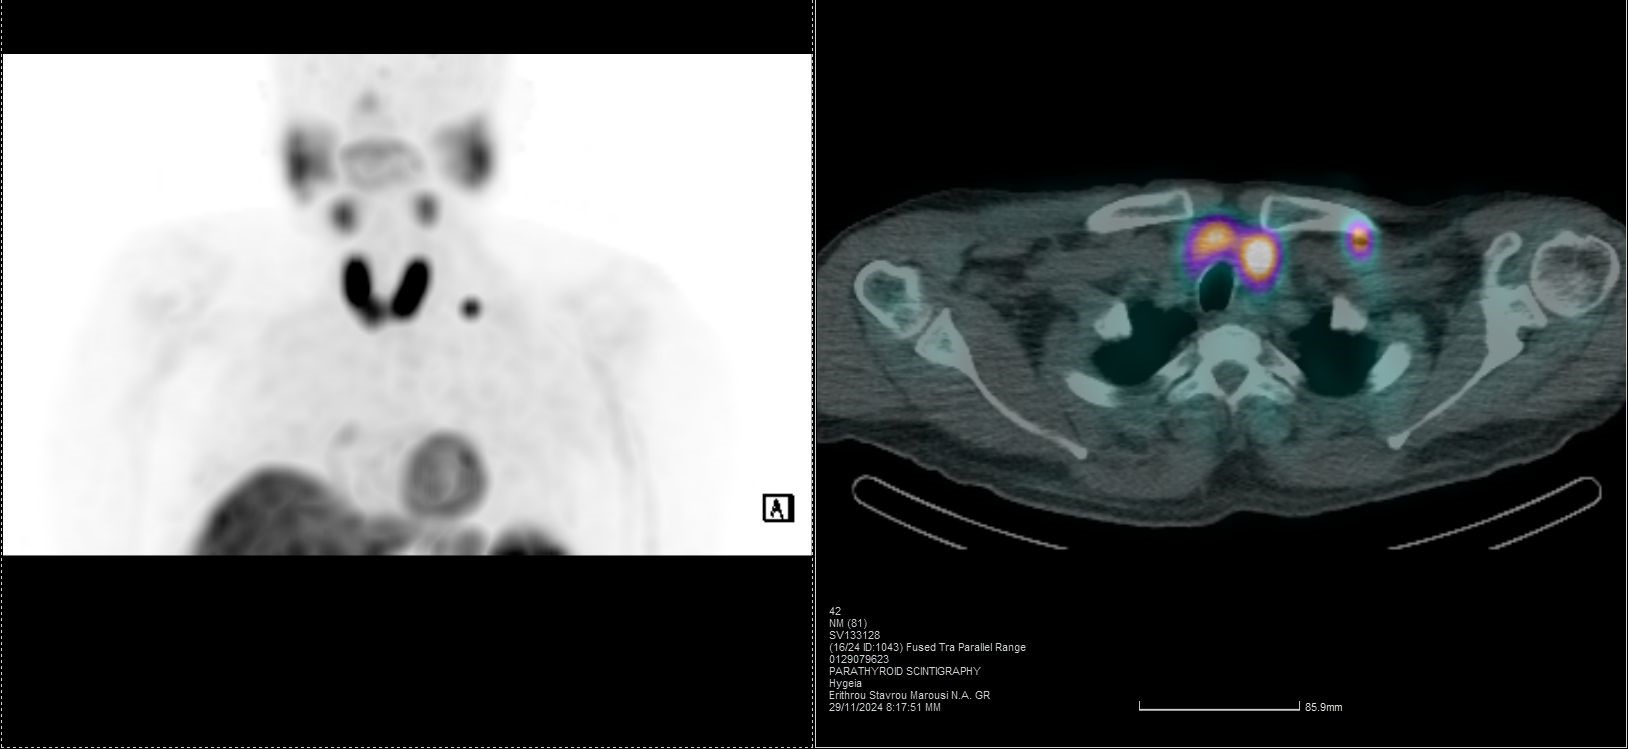

Οι περισσότερες διαγνωστικές εξετάσεις της Πυρηνικής Ιατρικής είναι γνωστές ως σπινθηρογραφήματα, τα οποία στη σύγχρονη εποχή πραγματοποιούνται με τη βοήθεια της γ-κάμερας (γ-camera) ή συστημάτων SPECT/CT, που επιτρέπουν απεικόνιση υψηλής ακρίβειας και λειτουργική ανάλυση σε μοριακό επίπεδο.

Tο Νοσοκομείο ΥΓΕΙΑ είναι το μοναδικό με πάνω από 15 χρόνια εμπειρία στην SPECT CT Aπεικόνιση. Από το 2024 διαθέτει δύο υπερσύγχρονες τομογραφικές γ-κάμερες της Siemens – Symbia Pro.specta SPECT/CT with myExam Companion. Πρόκειται για συστήματα τελευταίας γενιάς που συνδυάζουν υψηλή απεικονιστική ακρίβεια, χαμηλή δόση ακτινοβολίας και πλήρη αυτοματοποίηση της διαδικασίας. Με την χρήση ειδικού σύγχρονου λογισμικού (SIEMENS SYNGO) εξασφαλίζεται η μέγιστη ποιότητα εικόνας. Ειδικότερα οι γ-κάμερες χαρακτηρίζονται από τα εξής:

Όλες οι μελέτες Πυρηνικής Ιατρικής πραγματοποιούνται με SPECT/CT μέθοδο στις 2 υπερσύγχρονες SIEMENS Pro SPecta. Από το δυσδιάστατο στο τρισδιάστατο, από την υπόνοια στη βεβαιότητα.

ΟΛΕΣ ΟΙ ΜΕΛΕΤΕΣ ΜΕ ΤΗ ΔΙΑΓΝΩΣΤΙΚΗ ΥΠΕΡΟΧΗ ΠΟΥ ΠΡΟΣΦΕΡΕΙ Η SPECT/CT ΑΠΕΙΚΟΝΙΣΗ